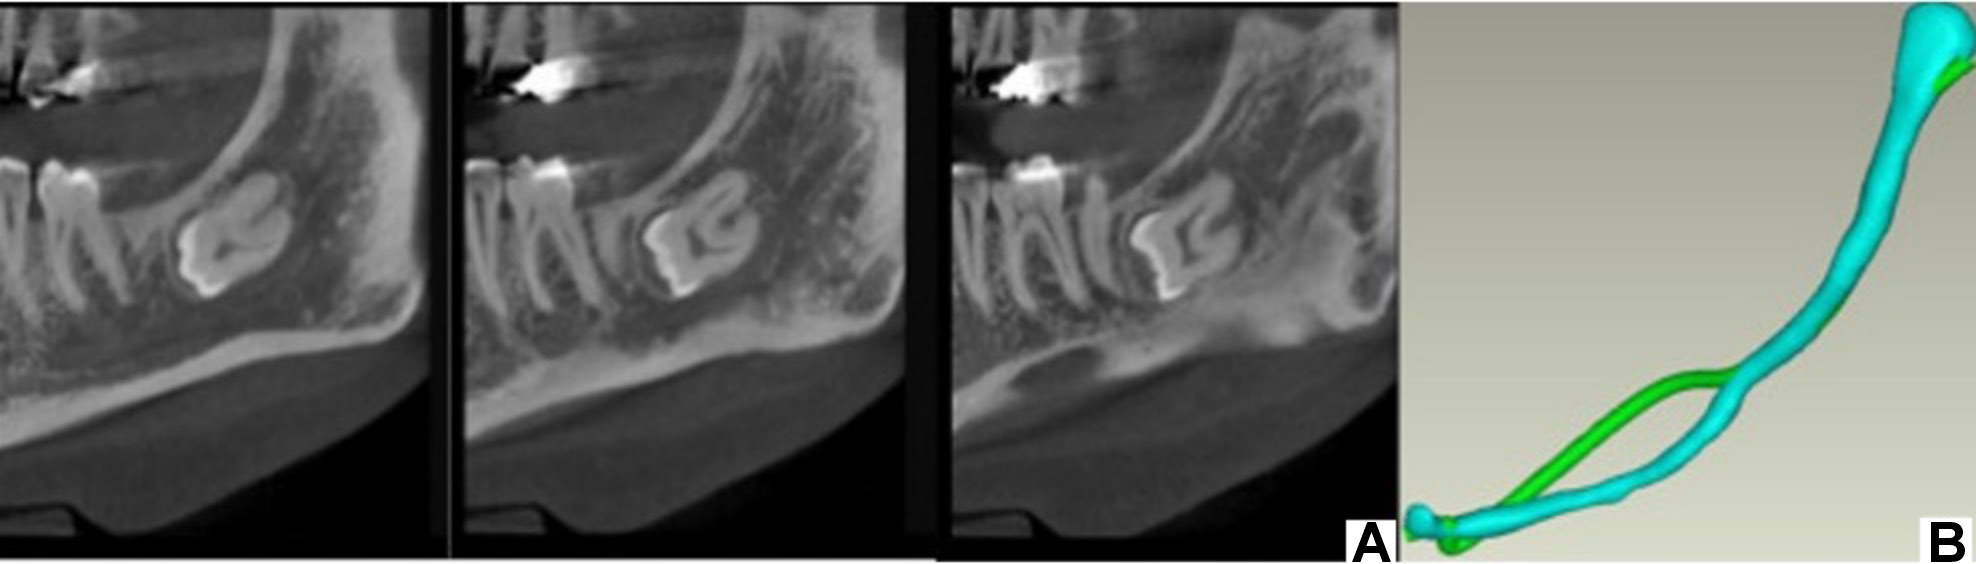

The IAC tracing, integrated into the Romexis® software, v. 6.2 (Planmeca, Helsinki, Finland), was employed to perform the semi-automatic segmentation (ground truth method) of the IAC on cross-sectional views of the 15 images collected. The tool requires the user to designate points along the canal, with the software automatically computing the canal’s pathway through progressive extension from these designated points. The task was performed by a trainee in oral and maxillofacial radiology (JI). During the segmentation process, the diameter of the cylinder representing the nerve replica was set at 1.50 mm. Subsequently, the IACs on both sides were saved as a single STL (Standard Triangle Language) file (Figure 2). The time required to complete the segmentation was recorded from the commencement of the process to its conclusion.

Automatic segmentation

Artificial intelligence was used to perform the automatic tracing of the IAC in the same anonymized images that had been previously segmented semi-automatically. The images were uploaded to Diagnocat (DGNCT LLC, Miami, USA), an online AI-based platform designed for the storage and processing of dental images based on a U-Net-like architecture algorithm. The AI algorithm automatically generated the IAC tracing and saved it as an STL file (Figure 3). The time required to complete the process was recorded, with an average Internet speed of 290 Mbps.